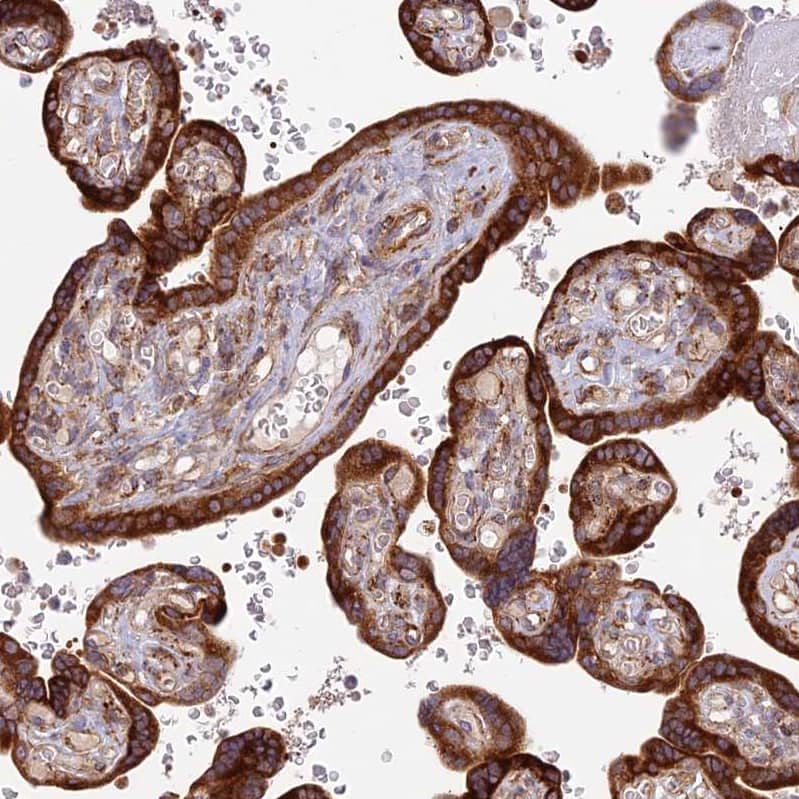

Staining of human placenta shows strong cytoplasmic positivity in trophoblastic cells.